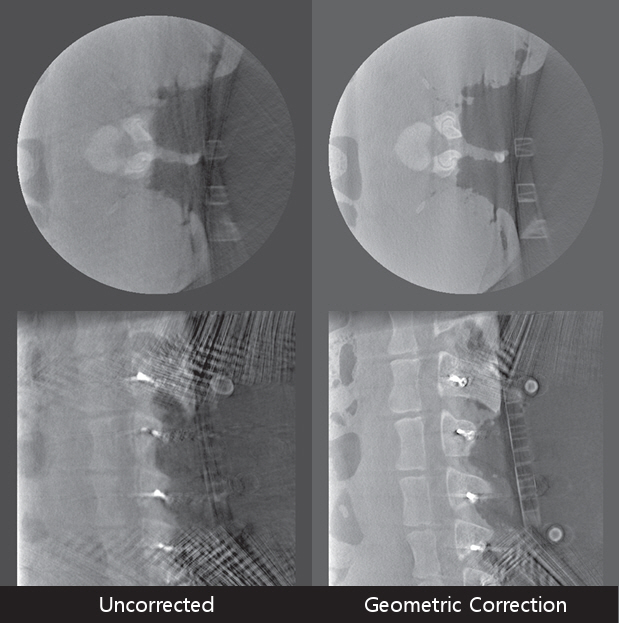

4. 기하보정

견고한 갠트리에 소스와 디텍터가 설치된 CT와 달리 모바일 C-arm CT 시스템은 아치형 형태의 갠트리를 사용하기 때문에 구조적으로 불안정한 형태를 가지고 있다. 그리고 다양한 각도에서 X-ray 영상을 촬영하여 CT로 재구성하기 때문에 촬영 시 소스와 디텍터의 투영 기하구조가 변형되어 기하학적 오차가 발생할 수 있다. 기하학적 오차는 CT 영상 화질에 영향을 주기 때문에 기하학적 오차를 보정하는 과정이 필수적이다[13].

모바일 C-arm CT는 기하학적 오차를 줄이기 위하여 그림 4와 같은 형태를 갖는 GCP(Geometry Calibration Phantom)를 이용하여 주기적으로 기하학적 정보를 보정해야 한다. GCP에 부착된 금속 비드(Bead)의 3차원 좌표를 사전에 측정한 후 팬텀을 촬영한 X-ray 투영영상의 비드와 비교를 통해 촬영 기하학적 정보를 계산한다.

GCP를 이용하여 얻어진 정보는 3차원 공간 좌표(x, y, z)와 2차원 투영영상의 좌표(u, v) 간의 역투영 관계를 정확하게 제공하여 그림 5와 같이 정확한 CT 영상 재구성을 할 수 있게 한다.

최근에는 모바일 C-arm CT 구조상 발생하는 불규칙한 흔들림을 실시간으로 보정하기 위하여 투영 영상과 AI를 이용하여 실시간 기하보정 연구가 진행되고 있다[14-16].